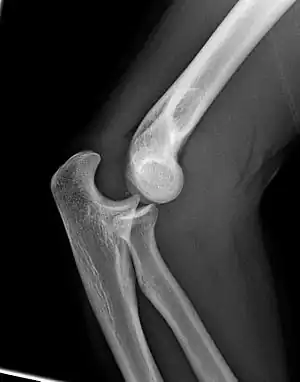

Left: Lateral X ray of a dislocated right elbow

Right: AP X ray of a dislocated right elbow

There are three bones at the elbow joint, and any combination of these bones may be involved in a fracture of the elbow. Patients who are able to fully extend their arm at the elbow are unlikely to have a fracture (98% certainty) and an X-ray is not required as long as an olecranon fracture is ruled out.[27] Acute fractures may not be easily visible on X-ray.[28]

Dislocation

X-ray of ventral dislocation of the radial head. There is calcification of annular ligament, which can be seen as early as 2 weeks after injury.[29]

Elbow dislocations constitute 10% to 25% of all injuries to the elbow. The elbow is one of the most commonly dislocated joints in the body, with an average annual incidence of acute dislocation of 6 per 100,000 persons.[30] Among injuries to the upper extremity, dislocation of the elbow is second only to a dislocated shoulder. A full dislocation of the elbow will require expert medical attention to re-align, and recovery can take approximately 6 weeks.